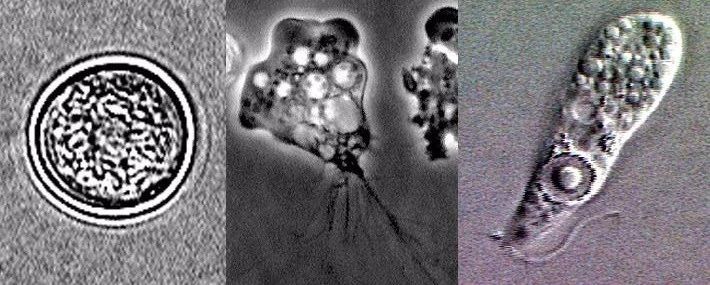

一般情况下,它会以三种形态生存,分别是滋养体、包囊、鞭毛。

最早被记录的阿米巴原虫图在环境安逸的条件下,福氏耐格里阿米巴原虫就以滋养体的形式存在水中。

生物期:囊肿、滋养体、鞭毛虫与其他寄生虫不同,在水中它们有时长出鞭毛,有时变出不同的手足。